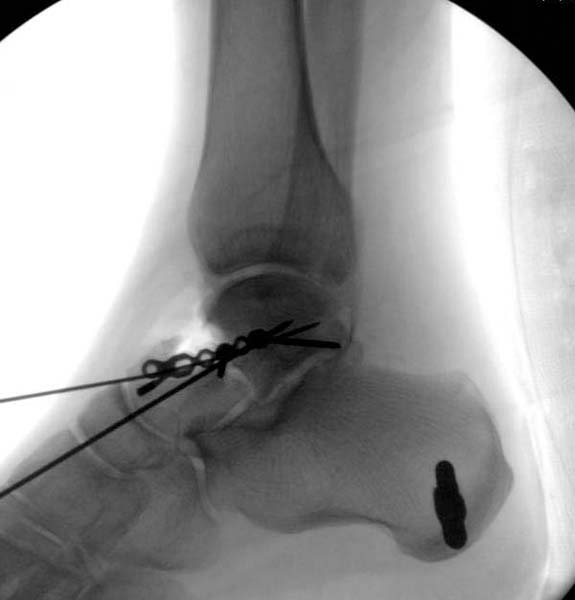

> Больная стабильная после хирургических мероприятии и получив добро,

> приступили к закрытому вправлению таранной кости с укладкой наружного

> фиксатора. Затем укладка больную на бок и открытый остеосинтез

> После спадения отека на стопе произведена фиксация тарана. Кстати, коллеги

> пересмотрели первоначальную консультацию по позвоночнику и на двух уровнях

> провели фиксацию. Из-за длительного постельного режима без нагрузки таз не